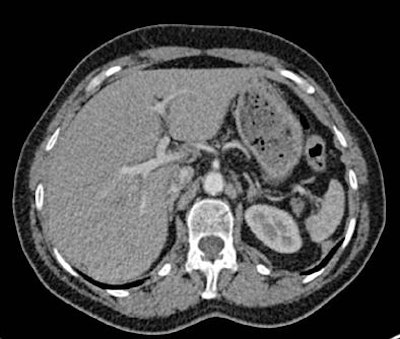

Images of the upper abdomen reconstructed using filtered backprojection (FBP) and the sinogram affirmed iterative reconstruction (SAFIRE) algorithm. Above, transverse image reconstruction with standard FBP at the level of the upper abdomen shows a high level of image noise. All images courtesy of Dr. Alkadhi Hatem.

Image reconstruction with raw data-based SAFIRE shows markedly reduced image noise and sharper depiction of vessel contours.Half the dose with far less noise